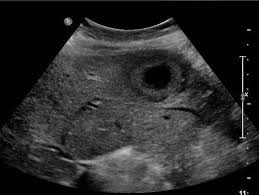

복부 초음파는 비침습적이며 방사선 노출이 없는 안전한 검사 방법으로, 초음파(ultrasound)를 통해 복부 내 장기들의 상태를 실시간으로 확인할 수 있는 진단 도구입니다. 복부 초음파로 알 수 있는 것 중에서는 특히 간, 담낭, 췌장, 비장, 신장, 방광, 대동맥, 소장, 대장 등의 상태를 파악할 수 있으며, 질환의 조기 발견에 탁월한 효과를 보입니다.

대표적인 복부 초음파로 알 수 있는 것(질환)

- 간암, 간종양: 실질 내부에 덩어리 유무 탐색

신장 및 요로계 질환

- 신장 종양, 낭종: 악성·양성 종양 여부 1차 판별